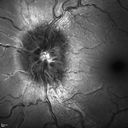

Optic Nerve Drusen - Buried and Not Calcified - Optical Coherence Tomography

34-year-old woman . Her vision is okay. She has optic nerve swelling, which is impressive and suggested she come here for an evaluation to distinguish between possible optic nerve drusen or optic nerve edema. Her brain scan was okay. Her vision is fine too. She is not getting headaches.

OD: Shows 1+ optic nerve thickening. I didn’t see any clear cut drusen.

OS: There is 3+ optic nerve thickening. Neither eye has any flame hemorrhages or at the edge of the optic nerve.

SPECTRALIS-SD-OCT SCAN: I did a spectral domain OCT over the optic nerve in both eyes, which shows what is consistent with optic nerve drusen. The outer nuclear layer is displaced and the outer plexiform layer is not swollen in either eye. I did nerve fiber layer scans in the right eye. The average nerve fiber layer thickness is 126 microns, which is well below the cut off you would expect with optic nerve edema, based on recently published reports. In the left eye it is a little trickier, because the optic nerve scan doesn’t properly trace the nerve fiber layer. There are a few artifacts, but temporally at least where it does trace the nerve fiber layer, she is within normal limits. When you get to the superior pole, it is a little bit edematous and then on the inferior pole, unfortunately the optic nerve edge is lost and doesn’t trace the optic nerve fiber properly.

FUNDUS PHOTOGRAPHY - AUTO FLUORESCENCE: The images show no hyper auto fluorescencent drusen in either eye.

1. PROBABLE OPTIC NERVE DRUSEN

DISCUSSION: I explained to the patient based on the spectral domain OCT scans over the optic nerve, I would say there is a 99 percent chance that these are optic nerve drusen. Because of the difficulties with the tracings in the left eye and also because the left nerve is so elevated, the nerve fiber layer thickness isn’t very reliable.